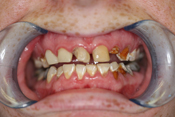

WORST TEETH Pictures from Warren Dentistry

This can happen to your teeth when proper Dental Hygiene is not practiced.

Patient 1